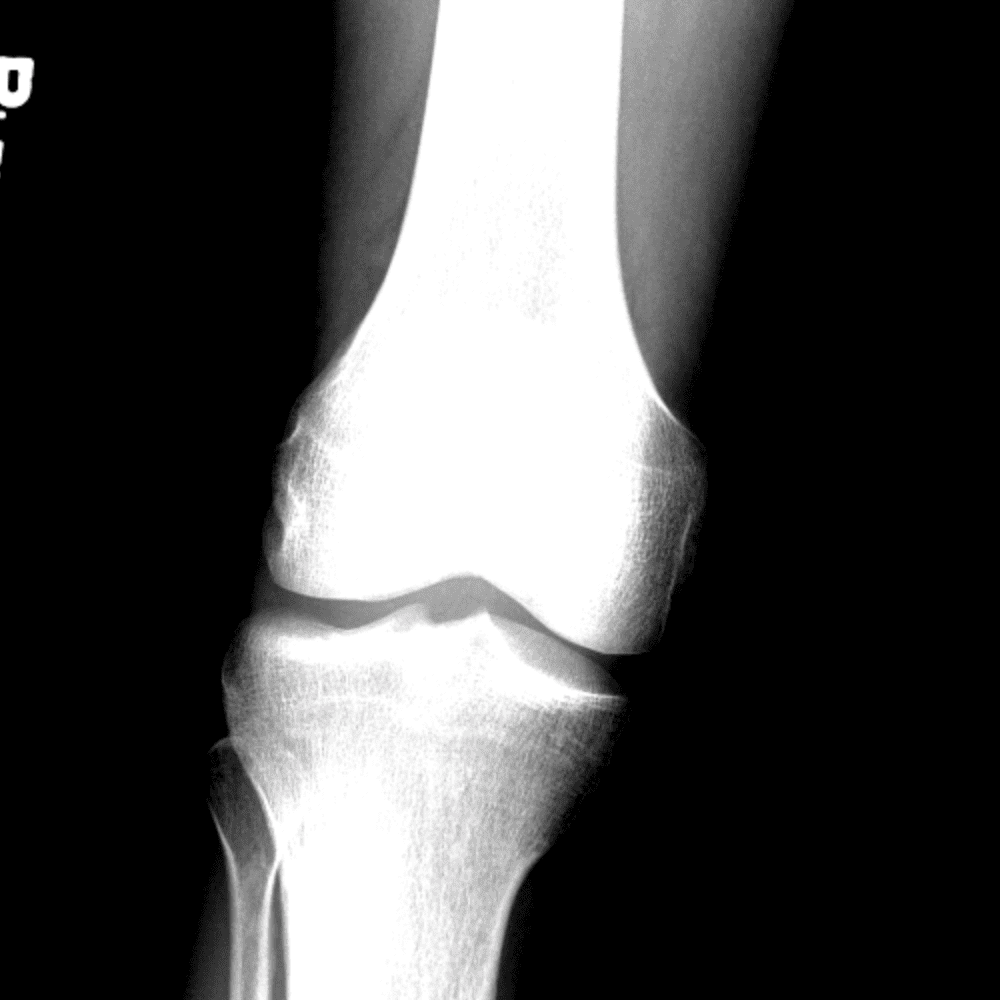

Simula o plantão incluindo casos sutis ou difíceis e alguns normais.